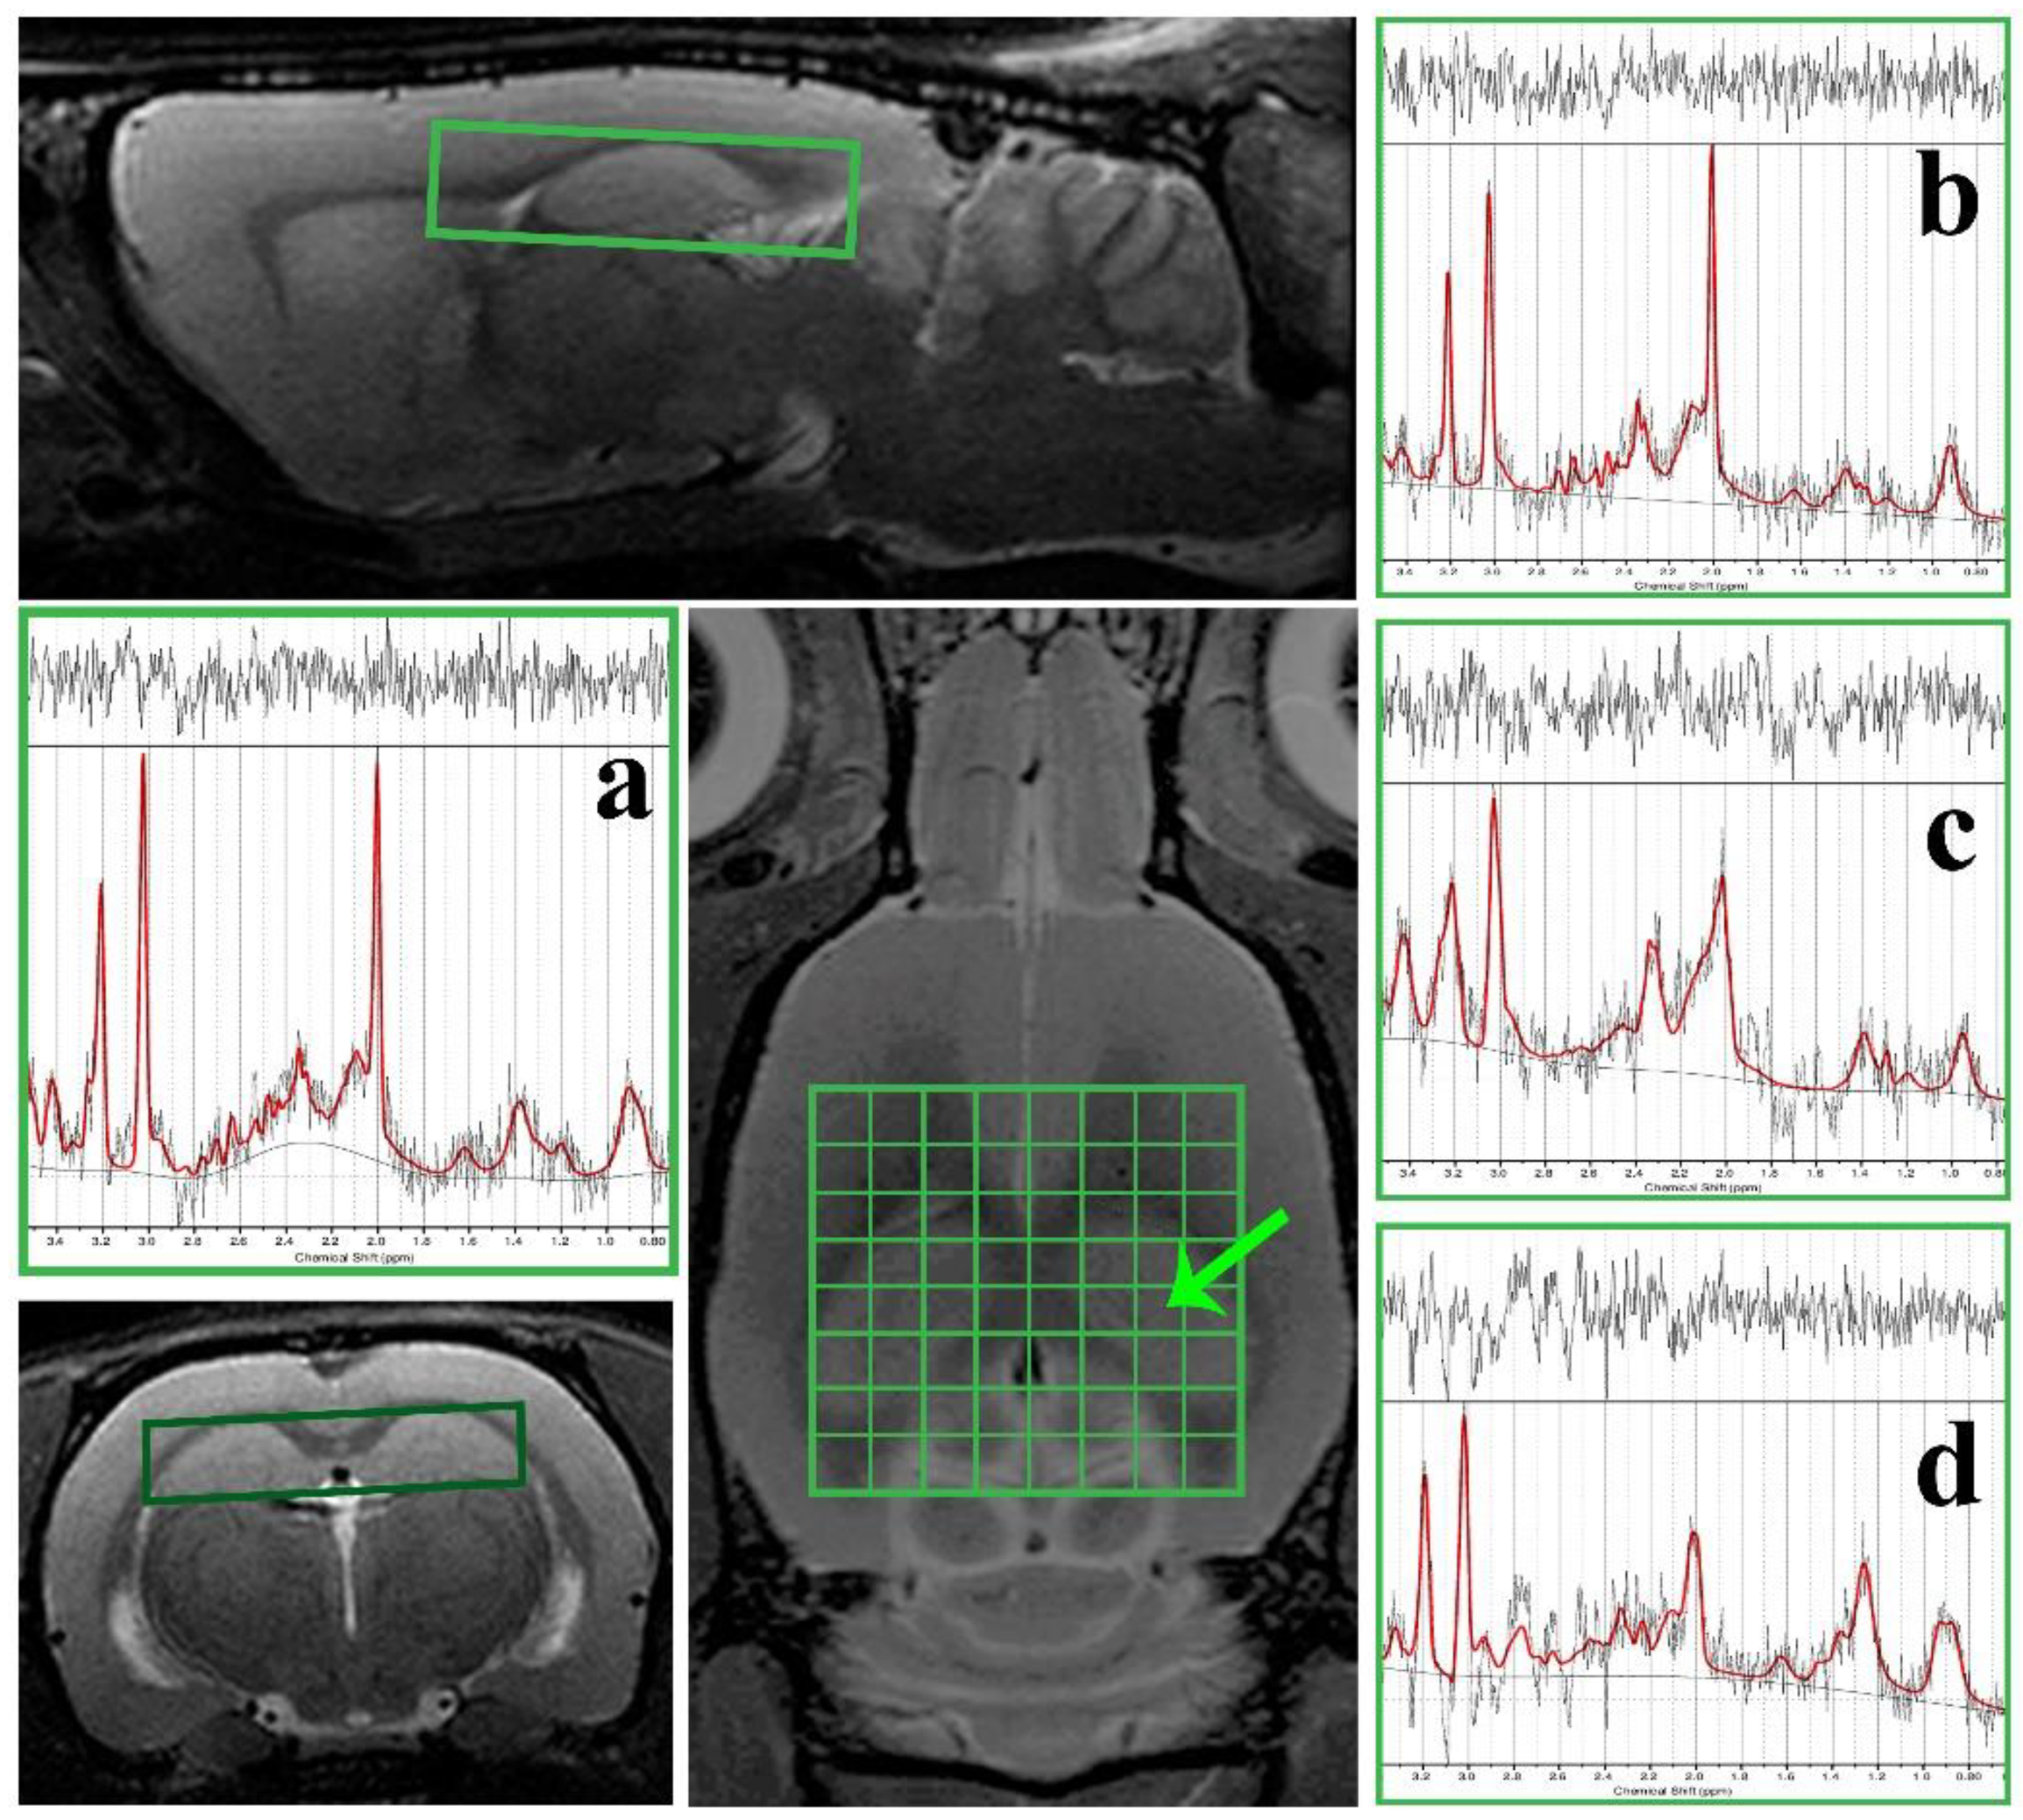

2.7. Image Analysis

3.3. 1H Magnetic Resonance Spectroscopy (MRS) Analysis and Volumetry

4.2. In Vivo Metabolic Changes in the Brain after Met Diet Induced hHcy and the Effect of Ischemia-Reperfusion Insult (IRI)